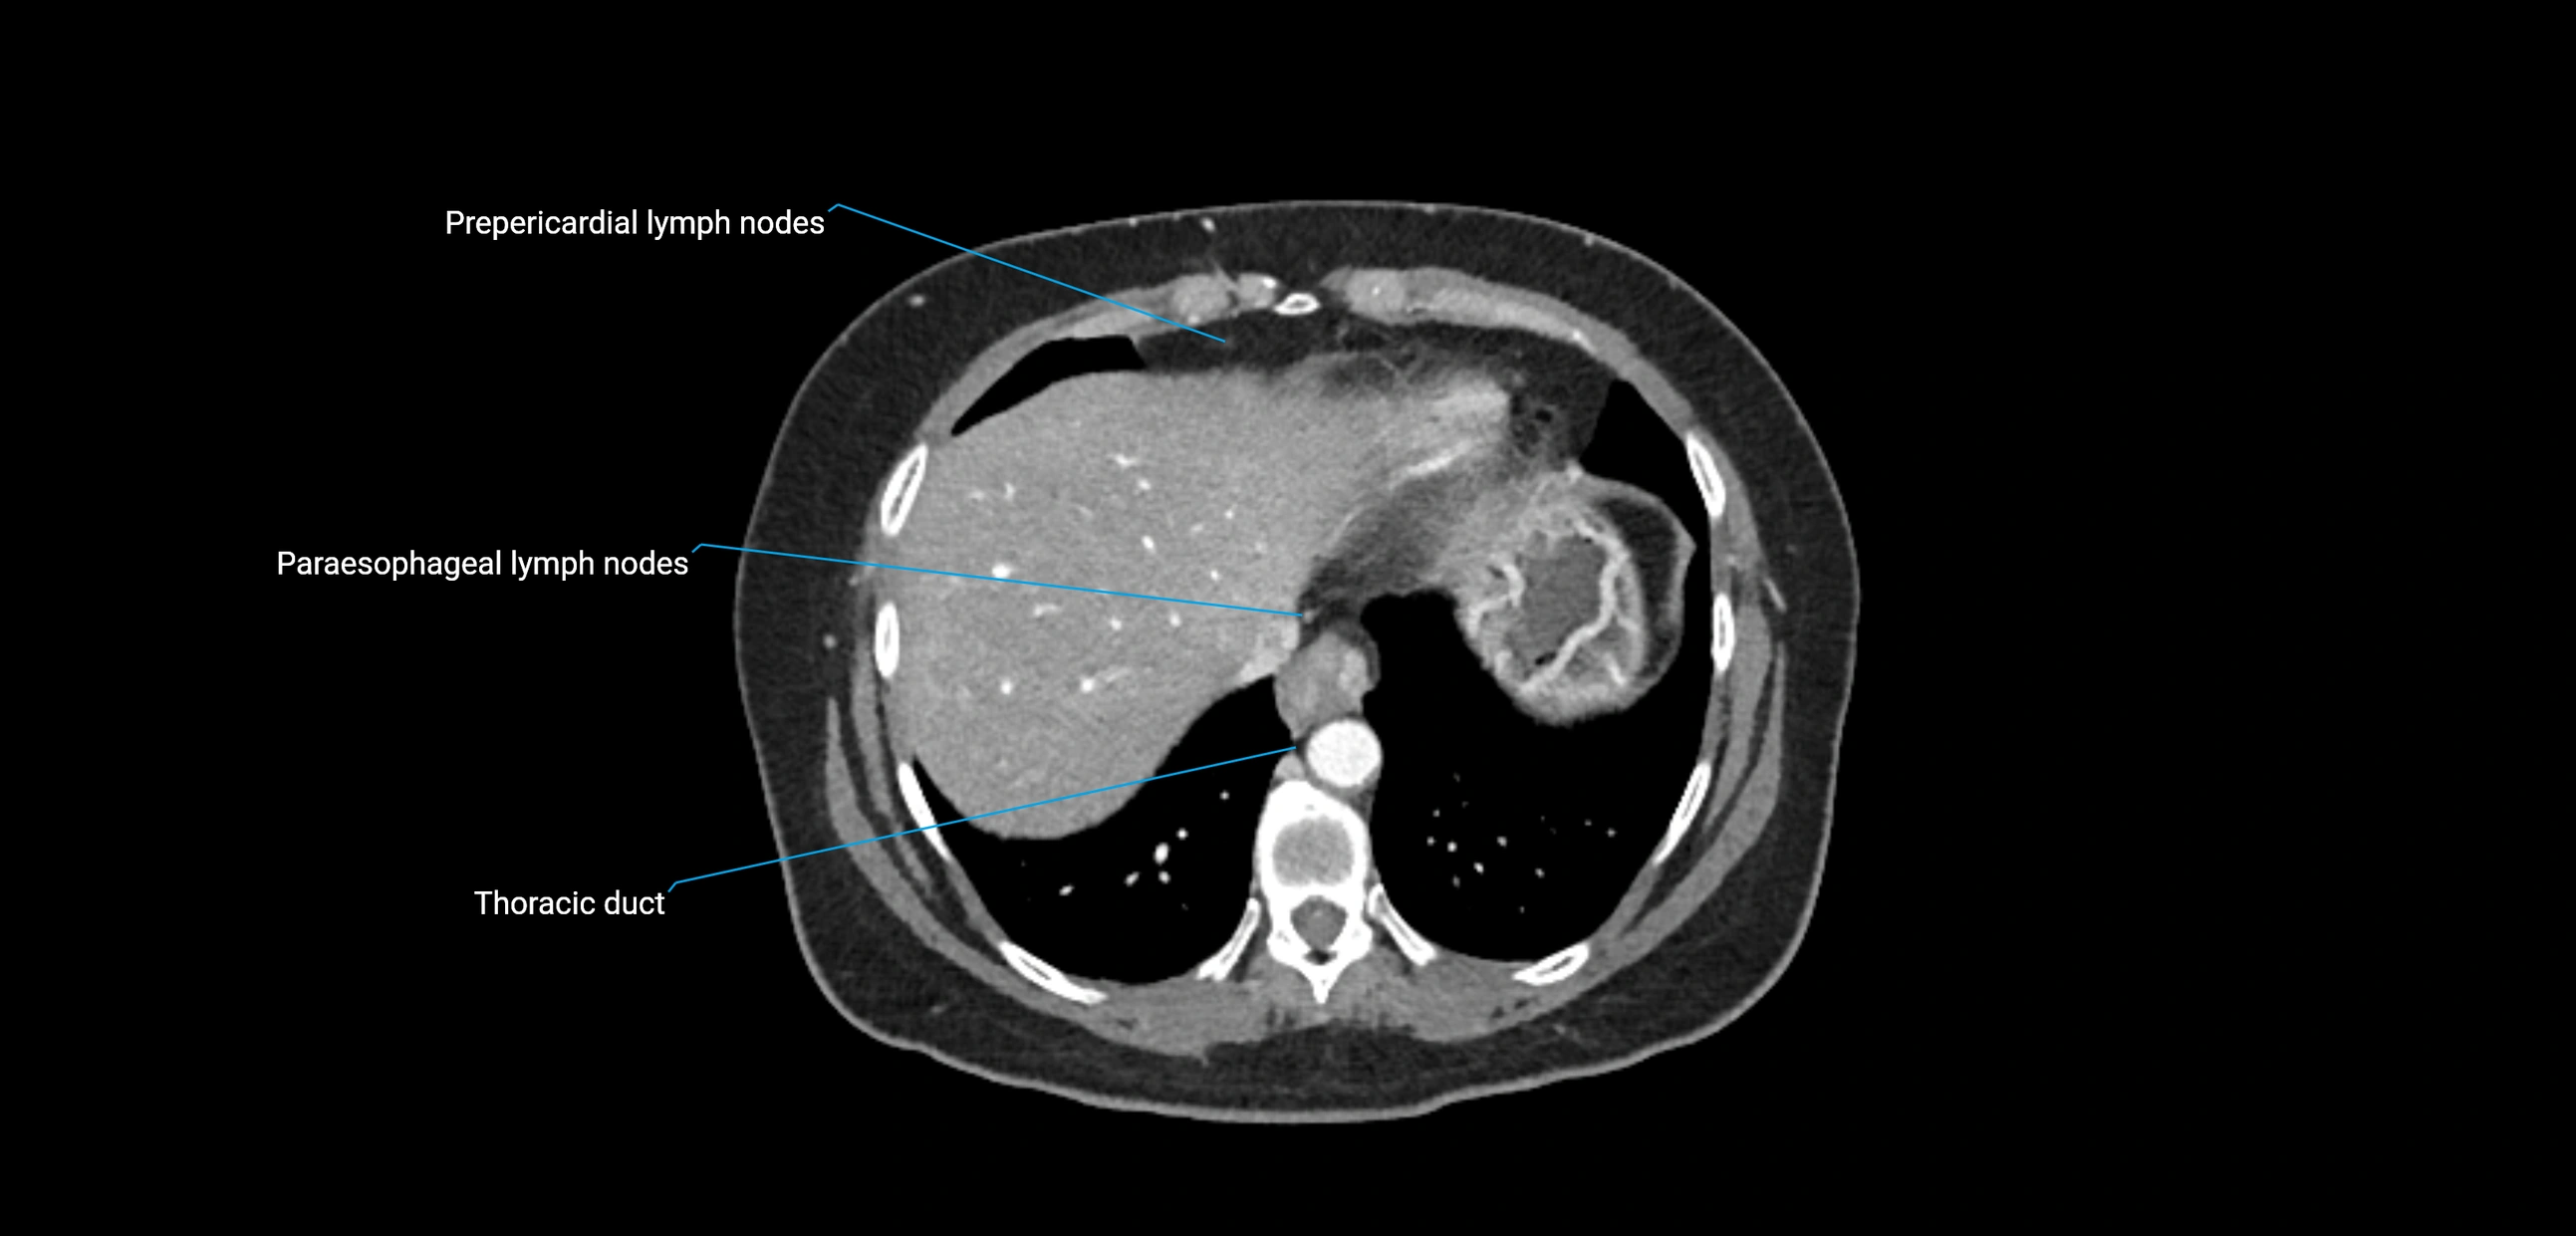

CT image

image